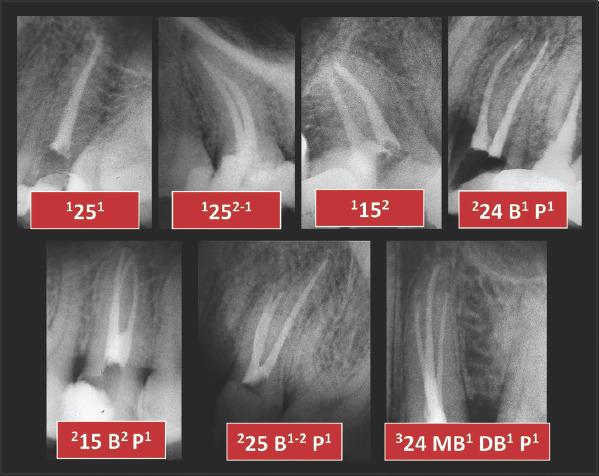

Adequate understanding and accurate characterization of normal and unusual root and canal morphology are essential requirements for successful root canal treatment. A new coding system for classifying root and canal morphology, accessory canals and anomalies has been introduced. In addition to technological advances related to experimental studies involving micro-computed tomography, the continuing clinical advances in magnification, illumination, imaging and intra-operative root canal treatment procedures have allowed clinicians to identify an increasingly wide range of anatomical variations in roots and canals in an attempt to achieve more predictable clinical outcomes. This review aims to provide a step-by-step explanation for the clinical application of the new coding system in dental practice, and to describe the anatomical variations in roots and canals for teeth scheduled for root canal treatment.

充分理解和准确描述正常和异常的牙根和根管形态是根管治疗成功的基本要求。引入了一种新的根管形态、副根管和异常分类编码系统。除了与涉及微计算机断层扫描的实验研究相关的技术进步外,放大、照明、成像和术中根管治疗程序的持续临床进展使临床医生能够识别越来越广泛的根和根管的解剖变异,试图实现更可预测的临床结果。本综述旨在为新编码系统在牙科实践中的临床应用提供逐步解释,并描述计划进行根管治疗的牙齿的牙根和根管的解剖变异。